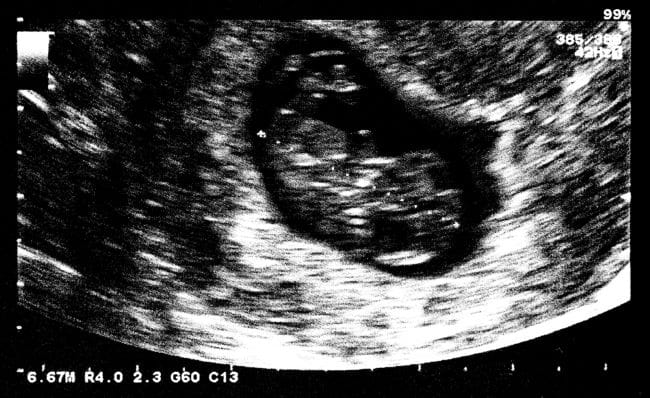

Janin 7 minggu menandakan bahwa kandungan Bumil sudah menginjak usia 2 bulan. Pada usia ini, ukuran janin masih sangat kecil, yaitu sekitar 1 cm atau seukuran dengan buah bluberi. Meski begitu, ukuran ini sudah bertambah 2 kali lipat dibandingkan saat janin berusia 6 minggu lho, Bun.

Bun, jangan khawatir bila menemukan ukuran kepala janin 7 minggu lebih besar dari tubuhnya saat melakukan USG nanti ya. Hal ini normal kok, karena pada usia ini otak janin sedang berkembang sangat pesat.

Saat melakukan USG 3D atau USG 4D, Bunda mungkin melihat ada dua titik kecil di kedua sisi kepala di mana telinga seharusnya berada. Nah, munculnya dua titik kecil ini menjadi tanda bahwa telinga janin 7 minggu, terutama telinga bagian dalamnya sudah mulai terbentuk nih Bumil.

Walau belum berkembang dengan sempurna, jantung janin 7 minggu sudah berdetak sekitar 150–180 kali per menit atau 2–3 kali lebih cepat daripada detak jantung normal orang dewasa.